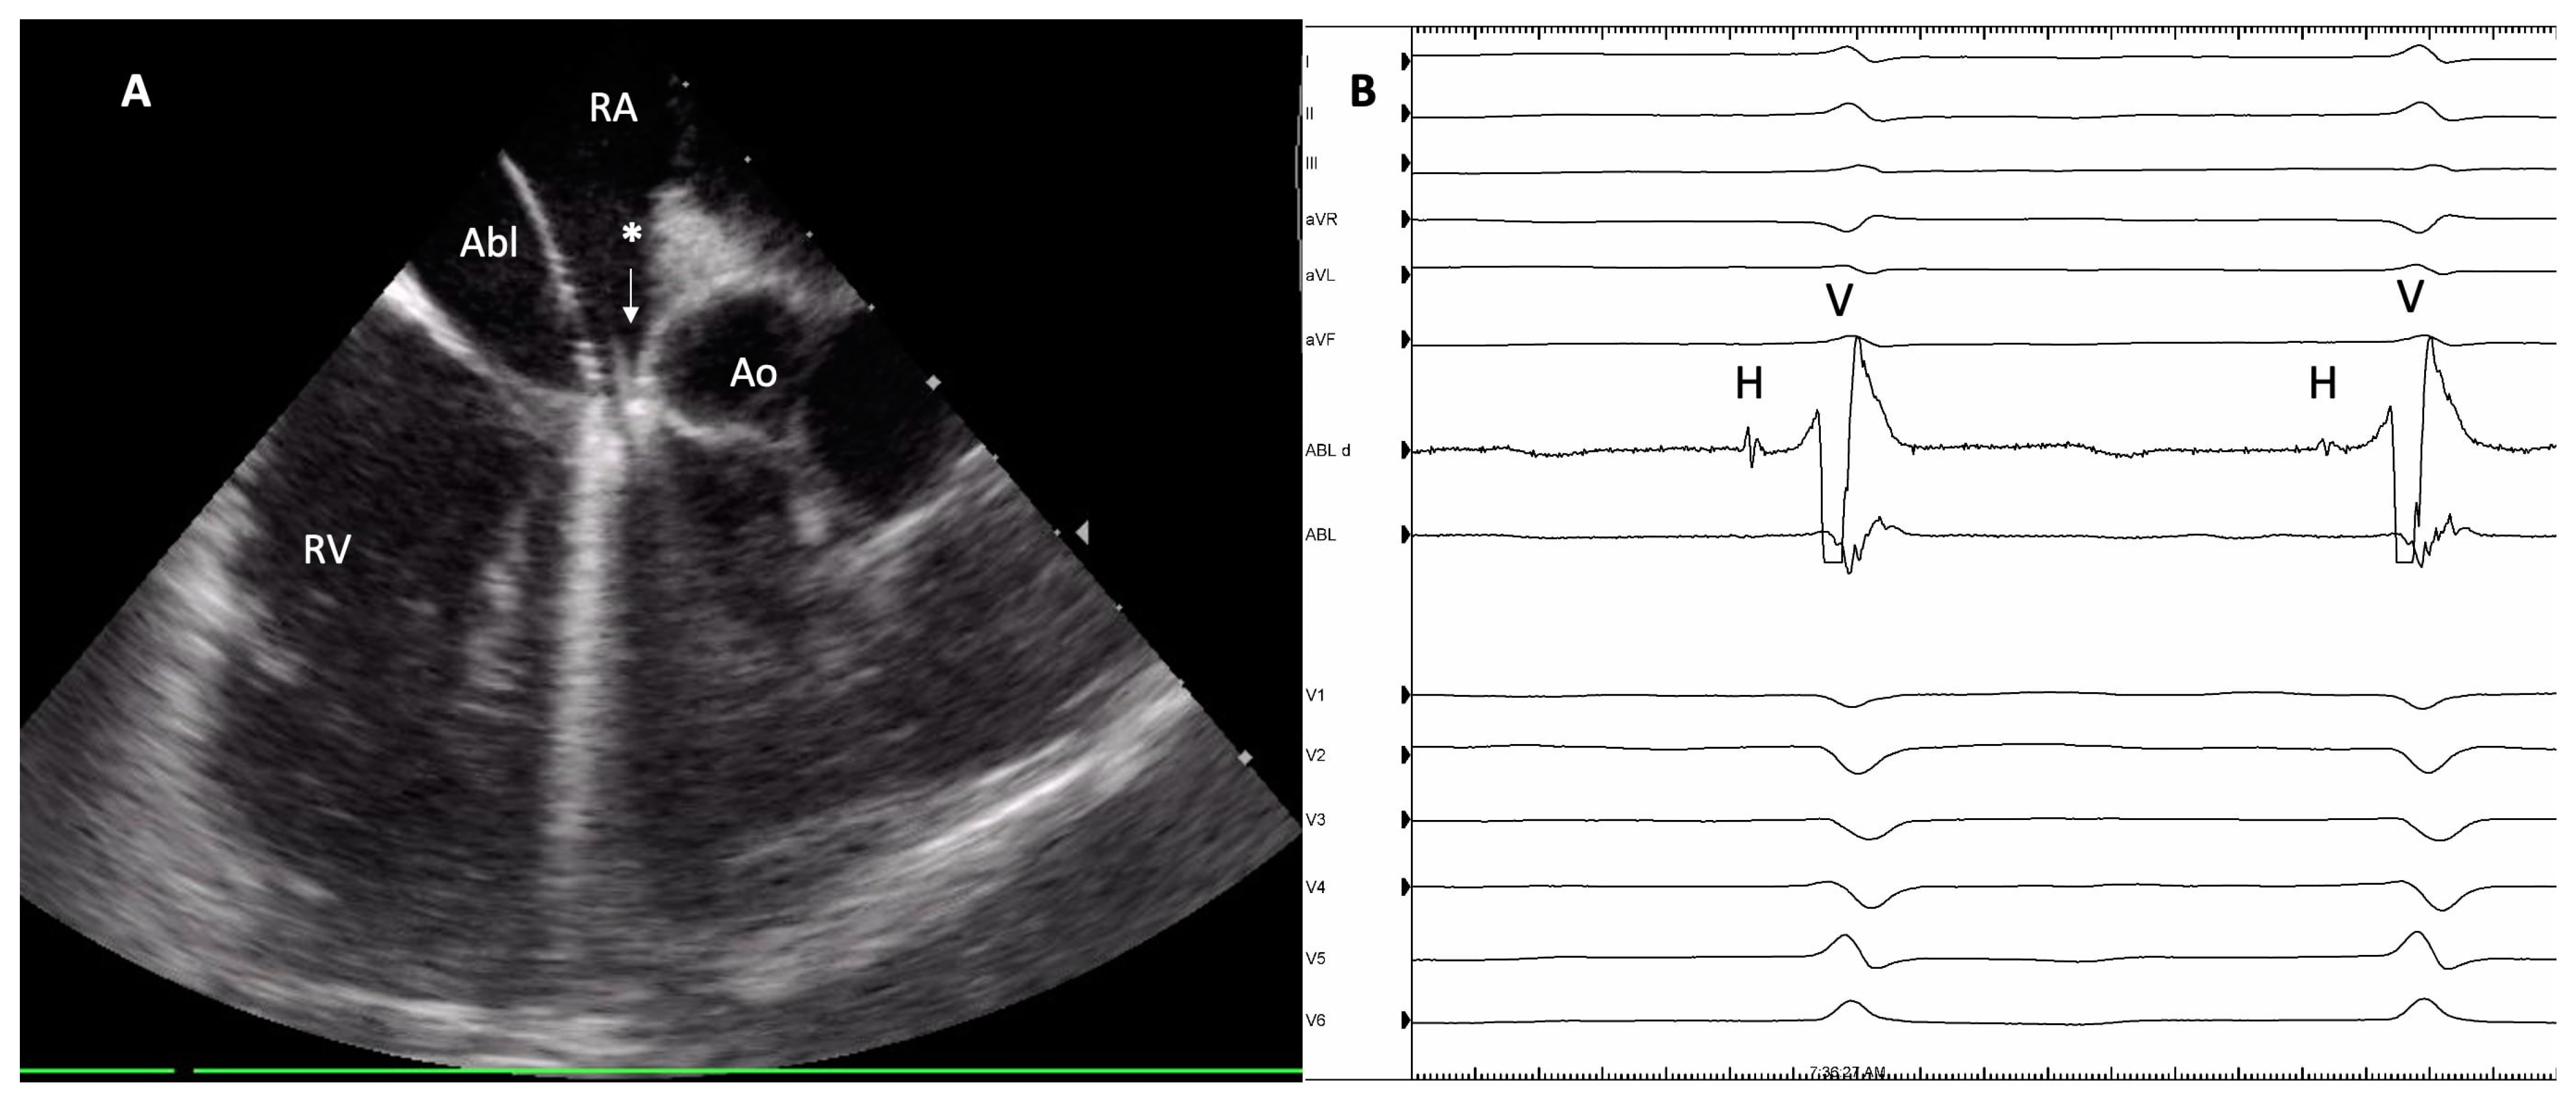

2.2. AV Node Ablation Procedures